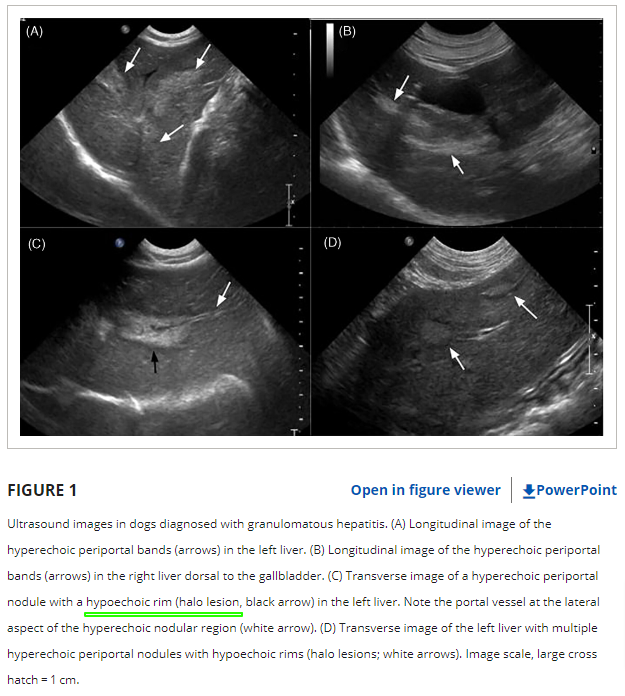

그리 자주 보이는 환자는 아니지만 육아종성 간염은 개에서 관찰되는 질환 중 하나이다. 비특이적인 초음파 소견으로 인하여 간과하기 쉽고 대증요법에 반응을 잘하여 예후가 좋은 편에 속하는 질환이기 때문에 잘 잊히는 그런 질환이기에 논문이 나왔을 때마다 환기를 해야 실제 케이스와 접했을 때 감별진단 리스트에 넣을 수 있어 소개한다.